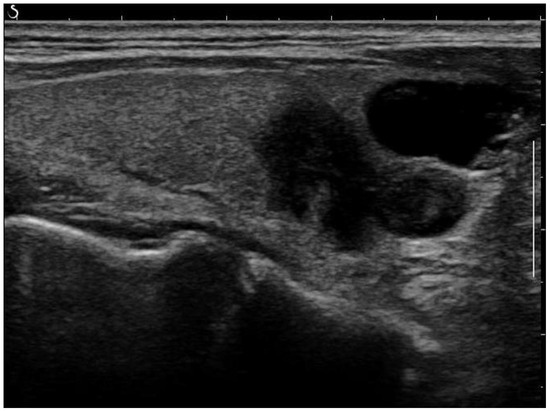

Removing Artefacts: Most of the artefacts are small white lines overlayed on the image. The objective of this process is to discard them while keeping the essential information present in the images. An anchor point (x, y) was used to automatically create a bounding box around artefacts. This box, defined by its width, height, and 4-connectivity method, helped to concentrate the processing around the artefacts. Without this step, there was a risk of inadvertently removing parts of the image that did not contain artefacts. Following this, morphological opening was applied to remove the small white thin lines corresponding to scale for annotation on the images while preserving the shape and size of larger objects in the image. A small structuring element was used to maintain the texture information. An example of a fully post-processed image can be seen in Figure 2.

Figure 2. Post-processed image after artefact removal and histogram equalization.